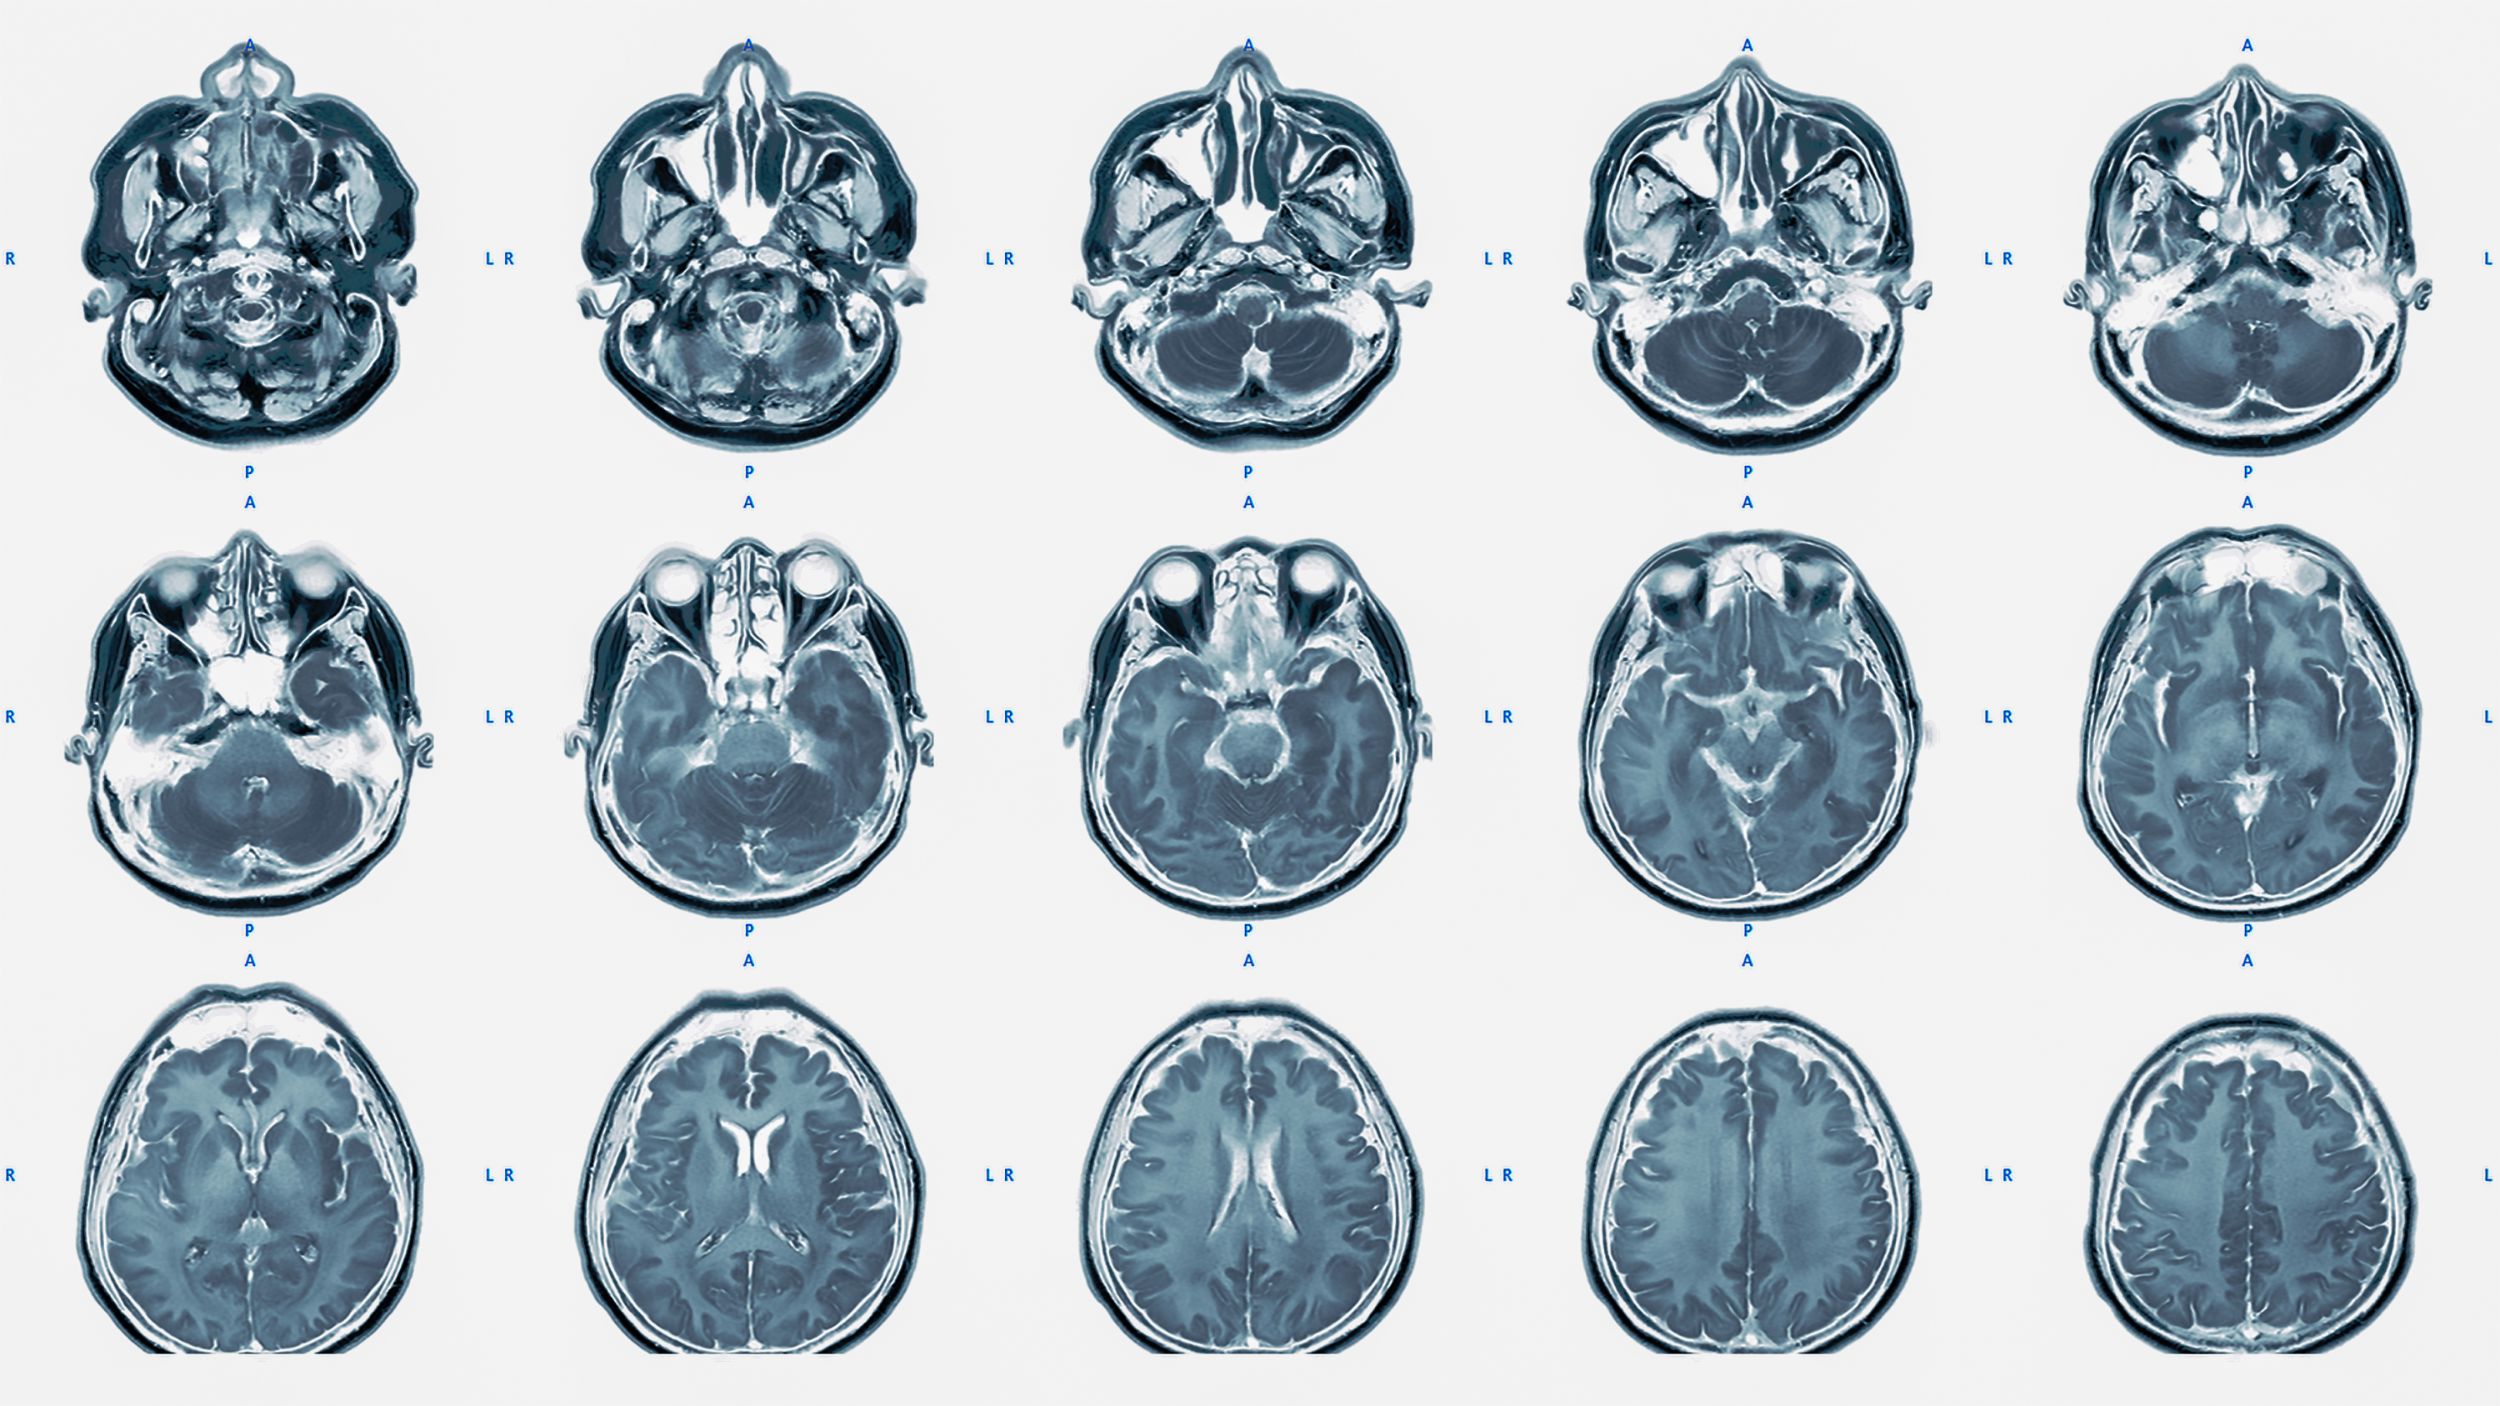

seltene Tumore MRI

Seltene Tumore

Die WHO beschreibt über 120 verschiedene Tumorarten des zentralen Nervensystems. Neben den häufigeren Hirnmetastasen, Meningeomen und Gliomen gibt es auch seltener vorkommende Tumoren wie Hypophysenadenome, Vestibularisschwannome oder Lymphome des zentralen Nervensystems.